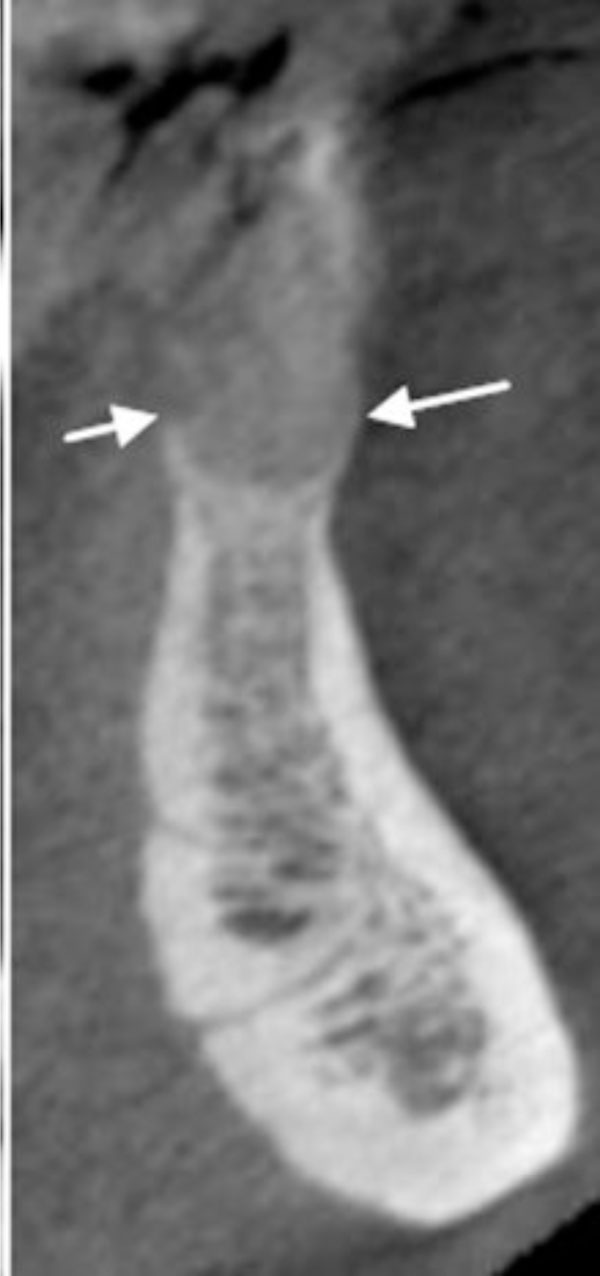

Fig. (1e).

Severe vertical bone loss is evident on this image of mandibular central incisors.

Fig. (1f).

The buccal and lingual cortical plates appear to be thinned and expanded. A well-circumscribed radiolucent lesion is present between the two mandibular central incisors.

A well-circumscribed, low-density, radiolucent lesion presented between the two mandibular central incisors. The buccal and lingual cortical plates appeared to be thinned and expanded (Fig. 1f).